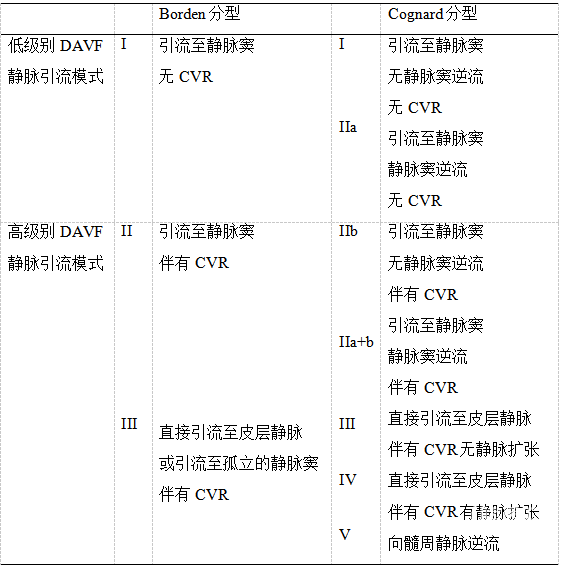

Cognard和Borden等人都证实了DAVF的病程进展与静脉引流模式密切相关,这也是传统DAVF分型的血流动力学基础。在这两种分型方法中,DAVF可大致分为低级别 (非侵袭性或良性, Borden I型, Cognard I–IIa型) 和高级别 (侵袭性或恶性, Bordon II–III型, Cognard IIb–V型) 静脉引流模式 (表1) 。低级别DAVF静脉引流的特点是引流至硬脑膜静脉窦,不伴有皮层静脉逆流;而高级别DAVF静脉引流特点是伴有皮层静脉逆流 (Cortical venous reflux, CVR) 。高级别DAVF静脉引流模式与颅内出血 (Intracranial hemorrhage, ICH) 、非出血性神经功能缺损 (Non-hemorrhage related neurological defect, NHND) 脊髓静脉引流异常的发生密切相关,并可根据分型预测其发生风险,分型越高ICH及NHND或脊髓静脉引流异常发生风险越高。

表1. DAVF根据颅内静脉引流模式分级

注:CVR皮层静脉逆流